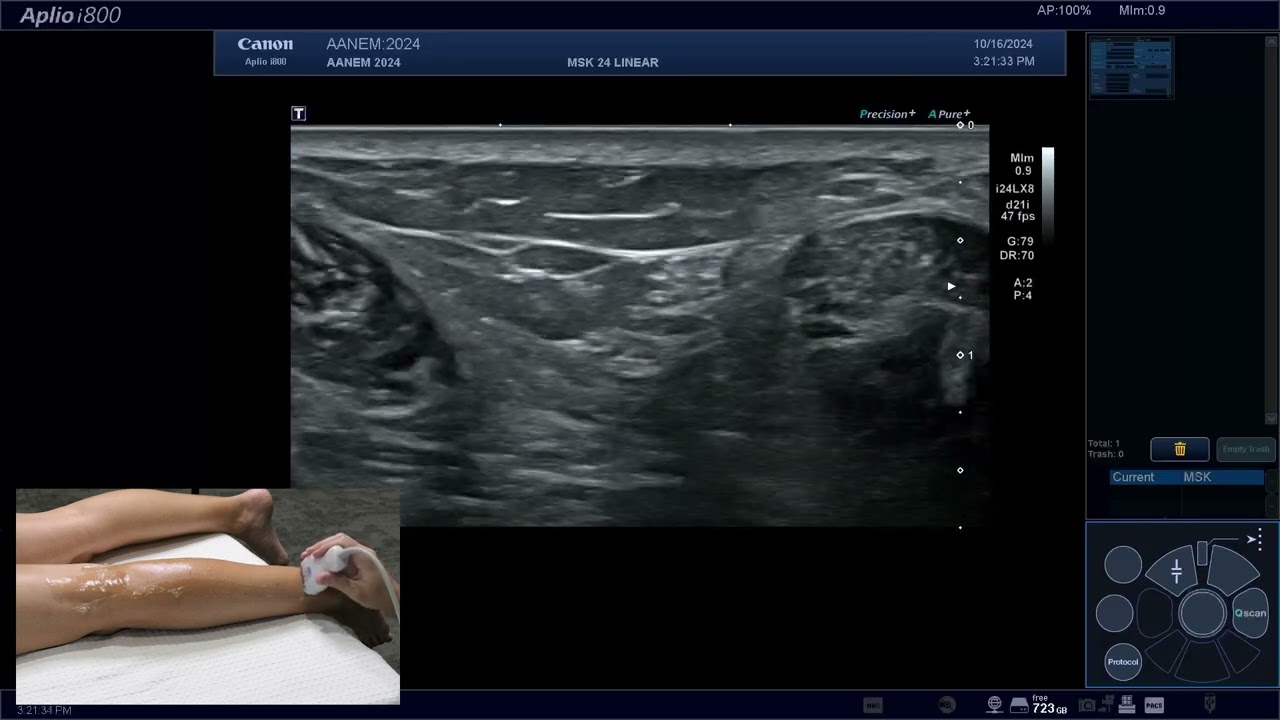

Скачать или смотреть Lessons From the Lab: Subacute Lower Extremity Weakness

Lessons From the Lab: Subacute Lower Extremity Weakness

Dr. Devon Rubin presents Dr. David Preston with a challenging case of a man with subacute lower extremity weakness. Enjoy the potpourri of information about anticoagulation, A waves, F waves, demyelination, ultrasound, Siri, and so much more! Visit our website for more information and educational materials ⁠education.aanem.org⁠.